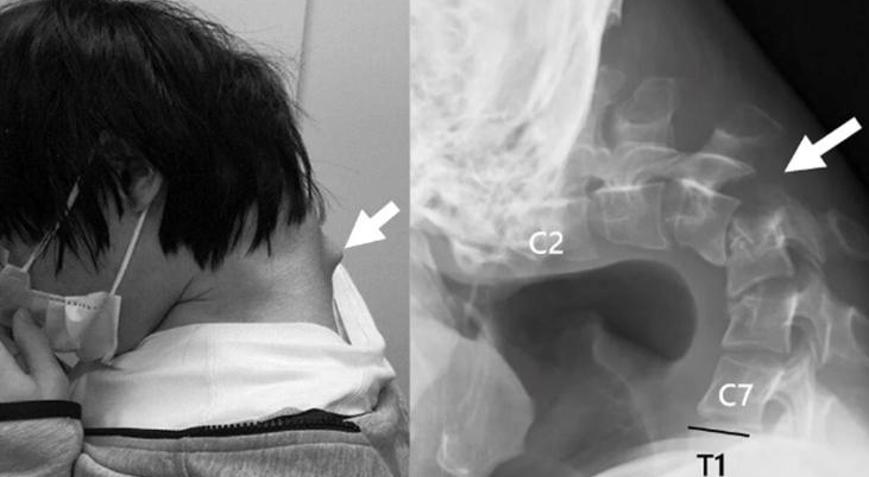

Bir MRI taraması, başının uzun süre doğal olmayan bir pozisyonda olmasının yıkıcı etkilerini gösterdi. Servikal omurgası hasarlıydı, pozisyonu bozuktu ve aşırı gerilmeden dolayı yara dokusu vardı. Omurgasında ciddi hasar ve deformasyon tespit edilirken, boyun kaslarının işlevini yitirdiği belirlendi.

25 yaşındaki adama, sürekli telefonuna bakması nedeniyle başını kaldıramamaya başlaması üzerine Düşük Kafa Sendromu teşhisi konuldu.

Operasyonda hasarlı omurlar ve dokular çıkarılıp, boynu hizalamak için vida ve metal çubuklar yerleştirildi. Ameliyattan altı ay sonra hasta başını kaldırmaya başladı, bir yıl içinde ise hareket kabiliyeti ve duruşunda belirgin iyileşme gözlendi. Doktorlar, genç yaşta ortaya çıkan bu vakanın nadir olduğunu belirtirken, “Düşük Kafa Sendromu”nun akıllı telefon ve tablet kullanımına bağlı olduğunu vurguladı.